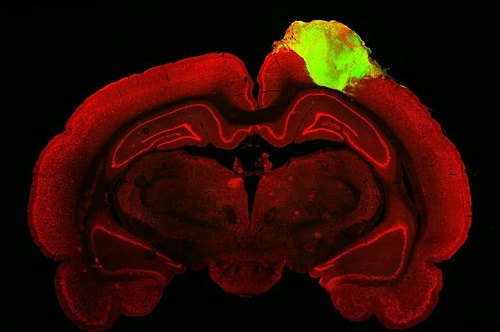

小鼠大脑(红色)与植入的人脑类器官(绿色)。图片来源:英国《新科学家》杂志网站

美国宾夕法尼亚大学研究人员将一束实验室培育的神经元(类器官)移植到视觉皮层受损的大鼠大脑中,以观察其是否能恢复该区域的部分功能。

在最新研究中,他们首先培养出可以发育成多种不同类型细胞的人类干细胞,80天后,这些干细胞被培养成大脑皮层细胞的三维组织,构成了大脑的外层,在视觉等多种功能中发挥关键作用。随后,他们将这些类器官移植到46只视觉皮层部分受损实验鼠的皮层内。

两个月后,植入的类器官开始出现神经元反应,研究人员在实验鼠观看屏幕上一系列图像时,将电极放入移植的类器官内测量到这些反应。研究人员表示,这表明神经元正在被整合到实验鼠的大脑内,并接管了其视觉系统的部分功能。

研究人员也比较了移植类器官的实验鼠与视觉皮层没有受损的实验鼠,结果表明,神经元的反应基本相似,但与未受损实验鼠相比,接受类器官移植实验鼠脑内对光产生反应的神经元更少。